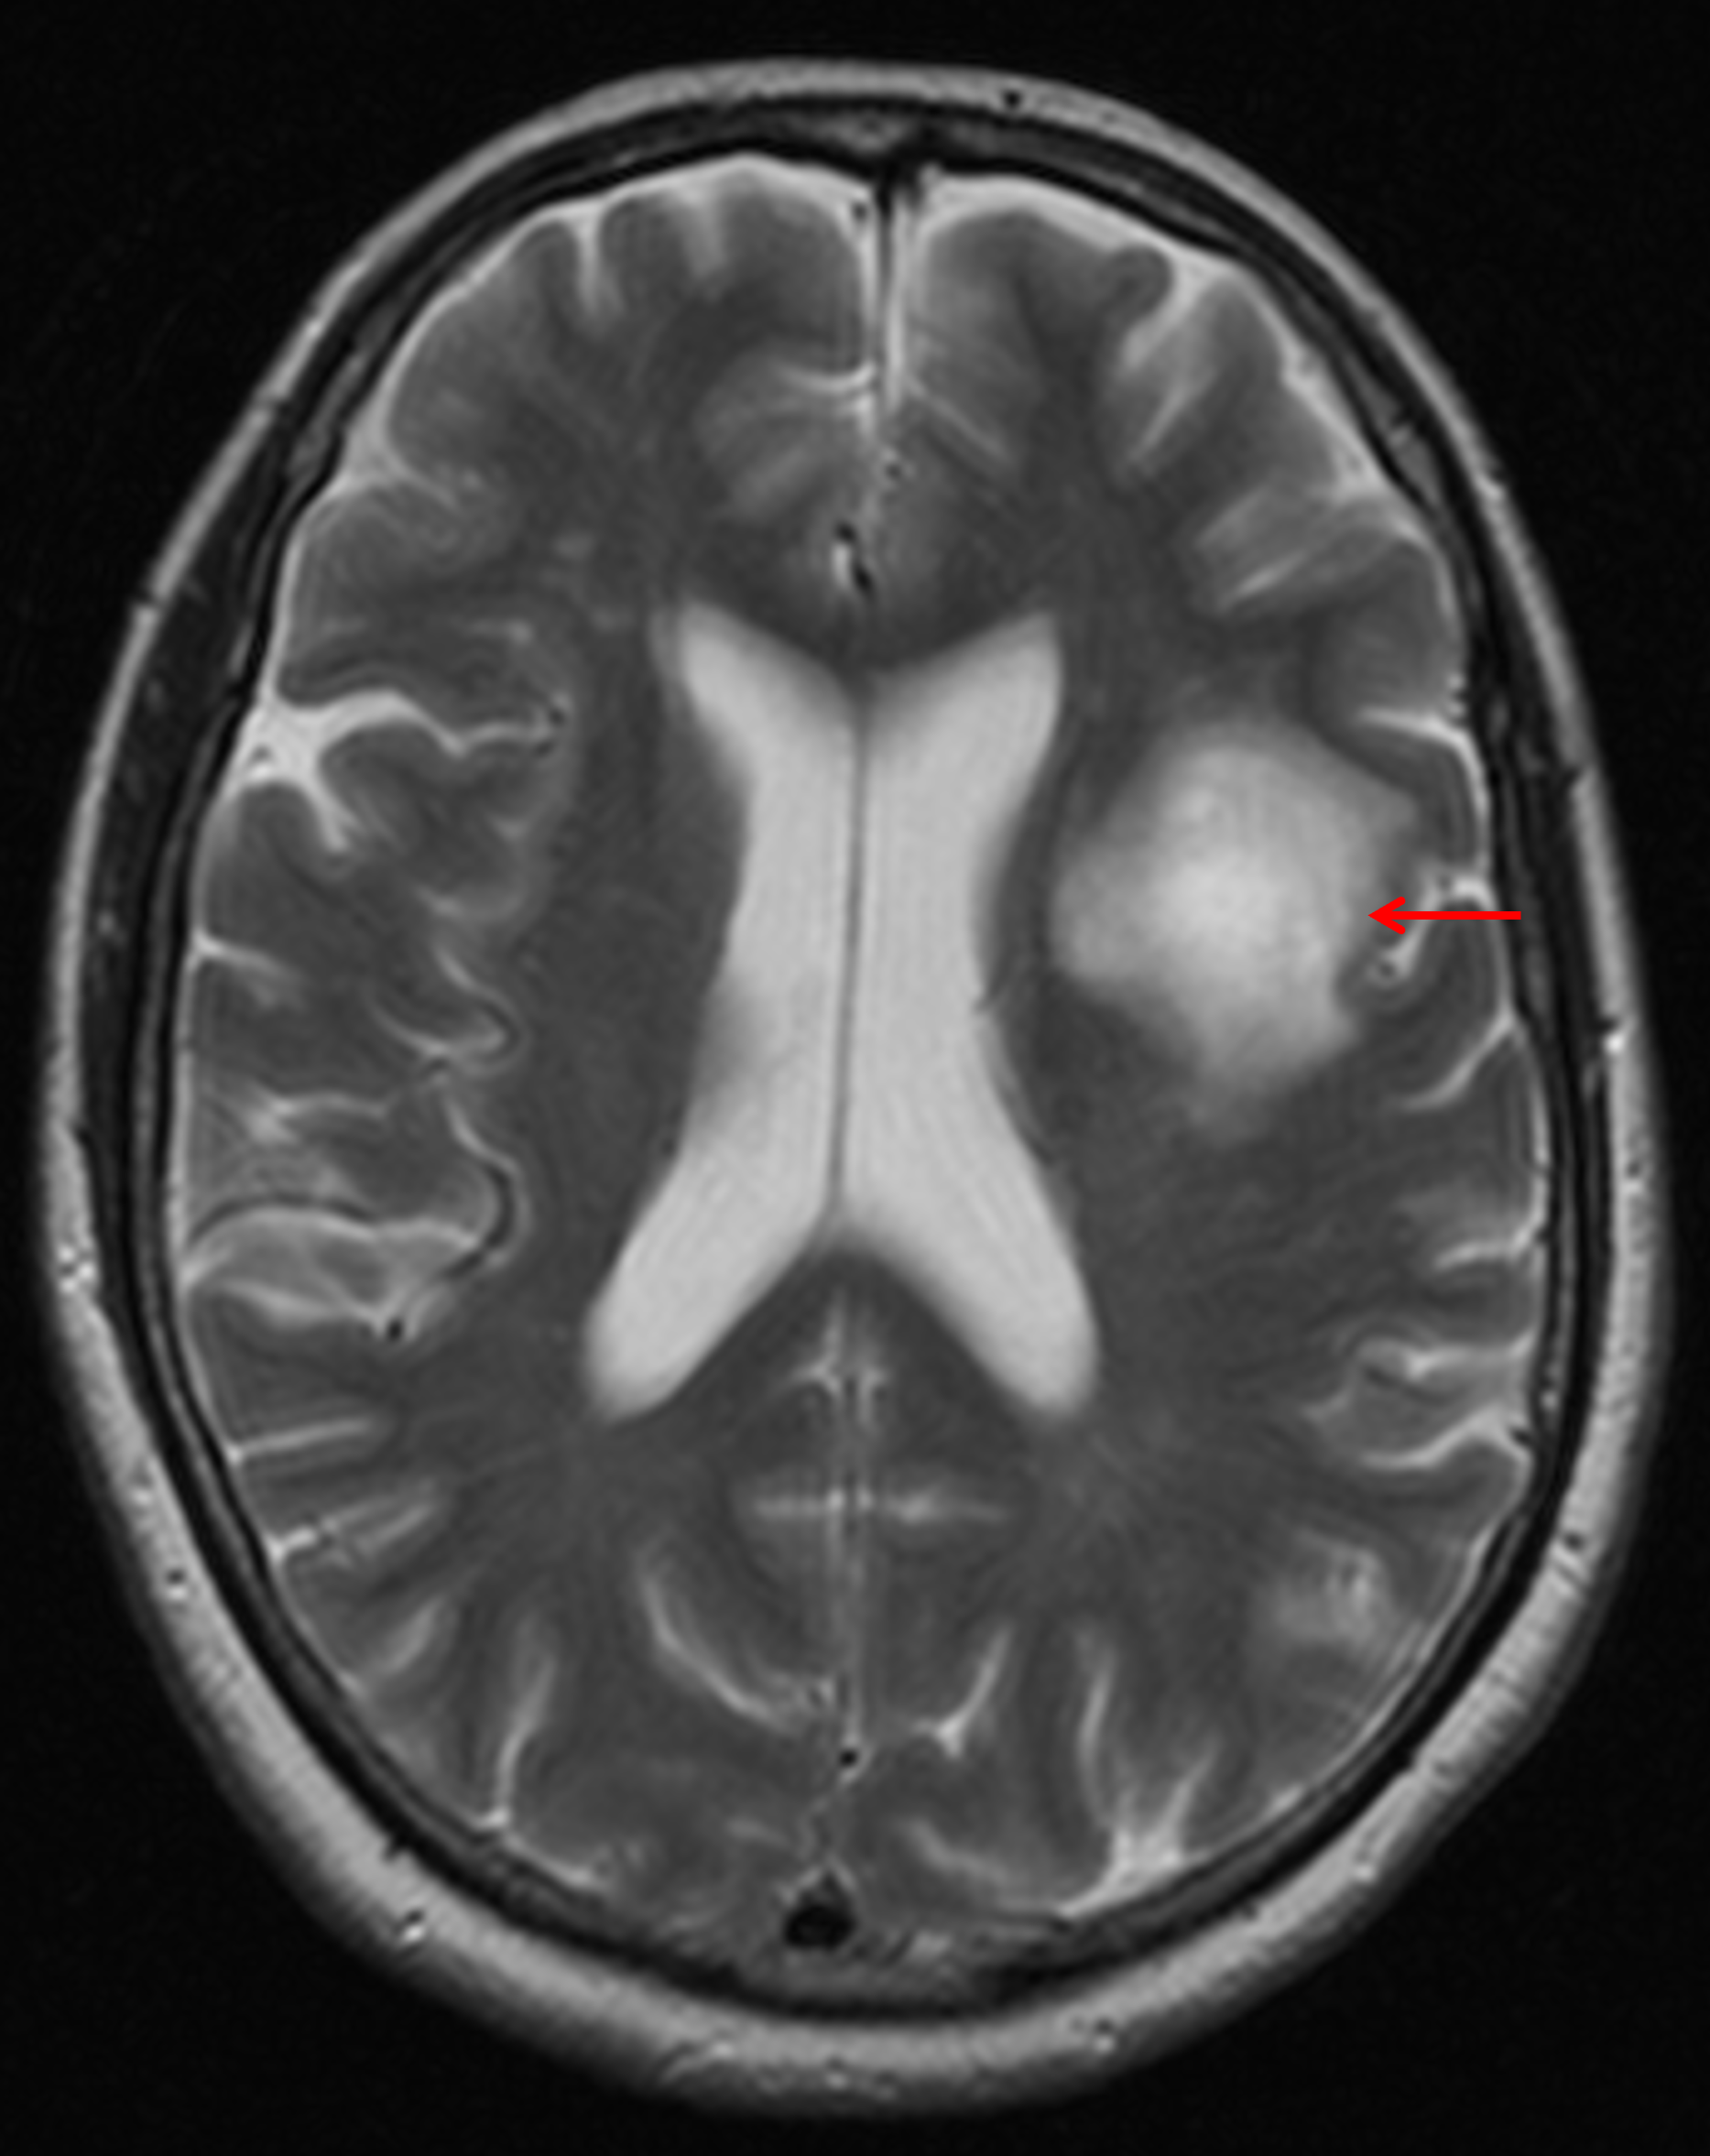

Age: 68

Sex: Female

Indication: Aphasia

Tumefactive demyelinating lesion